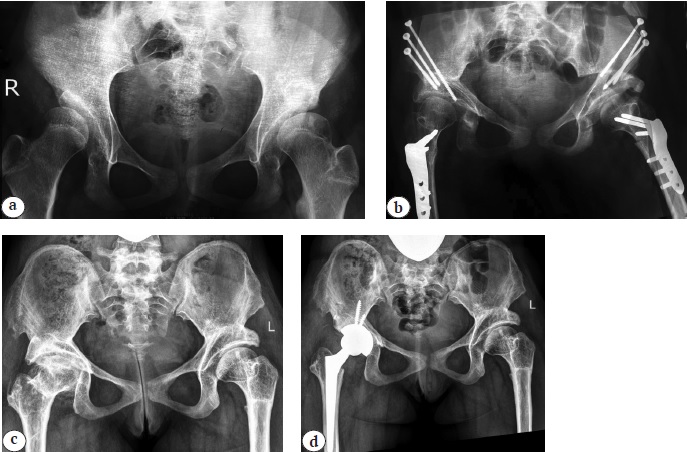

Рис. 5. История хирургических вмешательств у пациента 16 лет: а — рентгенограмма тазобедренных суставов на момент первичного обращения к специалисту в возрасте 11 мес. (дисплазия левого тазобедренного сустава III–1 степени по дополненной классификации D. Tönnis); b — попытка консервативного лечения (закрытое вправление бедра под наркозом с наложением гипсовой повязки в положении Lorenz 1), вправление не достигнуто; c, d — ближайший результат хирургической реконструкции левого тазобедренного сустава (релюксация с лизисом проксимального отдела бедренной кости в связи с перфорацией задней поверхности шейки бедренной кости клинком пластины с повреждением a. circumflexa medialis); e — среднесрочный результат хирургического лечения (патологический вывих с отсутствием проксимального эпифиза и шейки бедренной кости, формирующейся вторичной деформацией свода вертлужной впадины); f — рентгенограмма непосредственно перед проведением тотального эндопротезирования (грубая деформация вертлужной впадины, экстремально малый размер канала бедренной кости); g — среднесрочный результат тотального бесцементного эндопротезирования системой Zimmer Biomet (чашка Continuum® 44 мм, опорный аугмент Trabecular metal 50–30 мм, ножка Wagner cone® 13, пара трения: керамика — поперечносвязанный полиэтилен) с выполнением остеотомии большого вертела по T. Paavilainen и дилятационной остеотомии бедренной кости

Fig. 5. Surgical interventions sequence of a 16-year-old patient: a — X-ray of the hip joints at the initial specialist visit at the age of 11 months (grade III-1 left-sided hip dysplasia according to the supplemented D. Tönnis classification); b — an attempt at conservative treatment (closed hip reduction under anesthesia with a plaster cast put in the Lorenz position 1) — reduction has not been achieved; c, d — short-term result of the left hip joint surgical reconstruction (reluxation with lysis of the proximal femur due to damage of medial circumflex femoral artery caused by perforation of the posterior surface of the femoral neck with a blade plate); е — mid-term result of the surgical treatment (pathological dislocation with absent proximal epiphysis, femoral neck and forming secondary deformation of the acetabular arch); f — X-ray of the hip joints just before total arthroplasty (gross deformation of the acetabulum, extremely small femoral canal sizes); g — mid-term result of cementless THA performed with the Zimmer Biomet system (Continuum® cup 44 mm; Trabecular metal support augment 50-30 mm, Wagner cone® 13, ceramic-crosslinked polyethylene), the T. Paavilainen techniques of greater trochanter osteotomy and dilated osteotomy of the femur